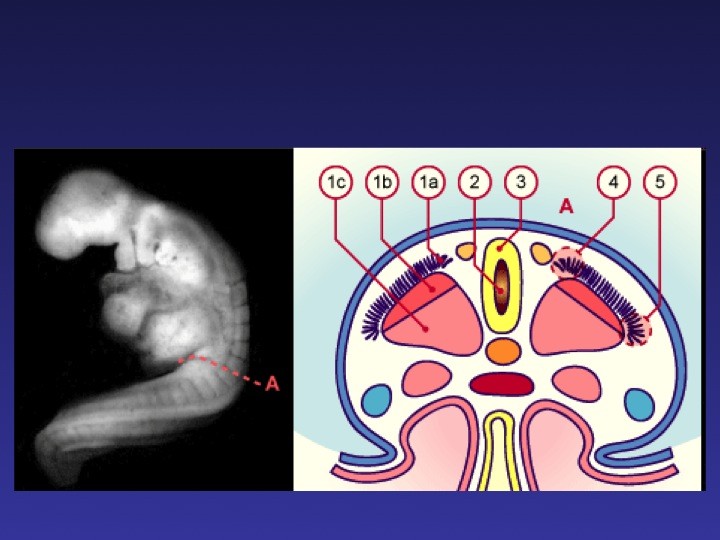

• 14.00 Approche anthropologique, embryologique, anatomique et neurochirurgicale

Jean-Guy PASSAGIA (Grenoble)

TABLE RONDE – La moelle attachée de l’enfant et de l’adolescent : diaporama 1